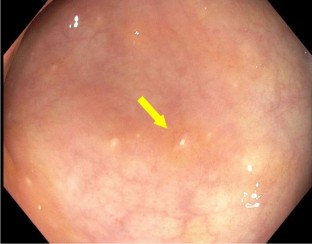

Fig. 3